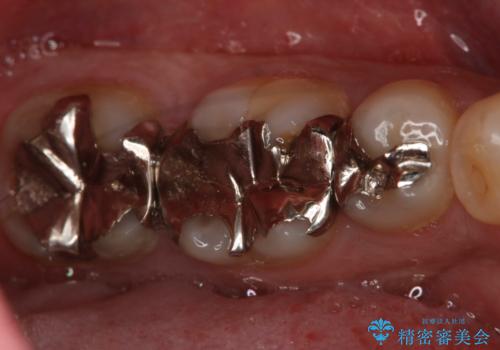

フルジルコニアクラウンによる銀歯のやり変え

- 左下6番の銀歯が不適であったためやり変えを勧めたところセラミックでの治療を希望された患者様です。

切削量などを考慮し、フルジルコニアクラウンでの治療を選択しました。

う蝕が深く切削量が多くなりましたが痛みなどは起きなかったので、予定通りフルジルコニアクラウンでの治療で進めました。